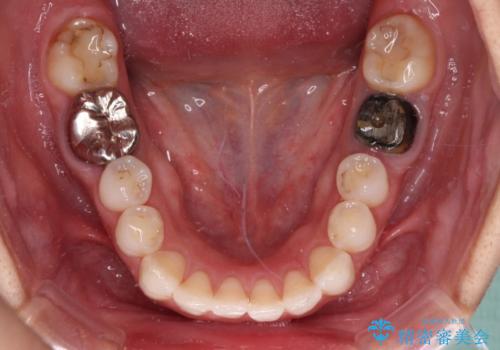

- 奥歯の銀歯が外れたことをきっかけに、全ての銀歯をセラミックに替えたいとのことで来院された患者様です。

第一大臼歯4本と、メタルインレーが装着されている2歯をセラミッククラウンならびにセラミックインレーにて補綴治療・修復治療を行うこととしました。